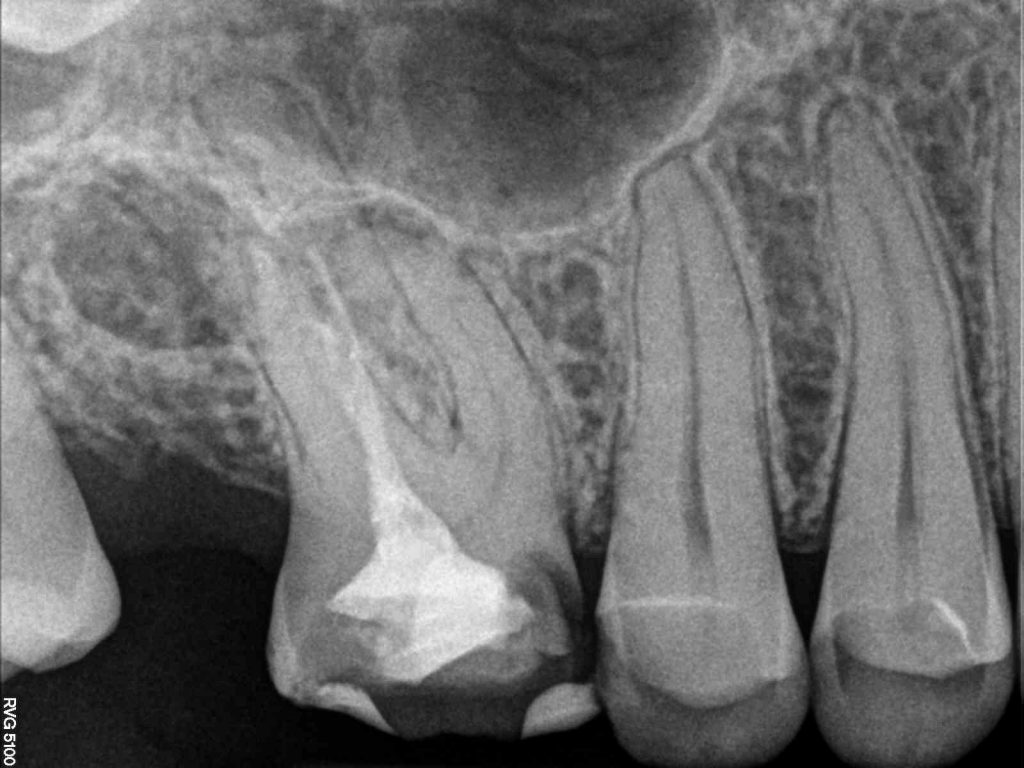

Streszczenie: Antyseptyczne leczenie kanałowe jest metodą leczenia przewlekłego zapalenia tkanek okołowierzchołkowych. W pracy przedstawiono opis przypadku, w którym postawiono powyższą diagnozę. Przewlekłe zapalenie tkanek okołowierzchołkowych często przebiega bezobjawowo, ze względu na znaczną resorpcję kości daje wyraźny obraz na zdjęciach rtg. Po zakończeniu leczenia konieczne są obserwacja oraz kontrolne zdjęcia rtg. po 3, 6 i 12 miesiącach.

Summary: The antiseptic endodontic therapy is a treatment procedure of the chronic inflammation of periapical tissues. The paper presents a case in which the above diagnosis was made. Chronic apical periodontitis is often asymptomatic; due to significant bone resorption it gives a clear image in X-ray images. After the treatment, it is necessary to monitor a patient and control X-ray images after 3, 6 and 12 months.

Przewlekłe zapalenia tkanek okołowierzchołkowych (PZTO) toczą się powoli, bezobjawowo, miesiącami lub latami. Wykrywane są w fazie zaostrzenia (chory szuka pomocy u lekarza) lub przypadkowo na zdjęciach rtg. wykonanych w celach diagnostycznych. Ich przyczynami są czynniki zakaźne (bakterie znajdujące się w miazdze w stanie rozpadu zgorzelinowego) oraz niezakaźne (chemiczne, termiczne, mechaniczne, autoalergiczne). Pierwszym objawem radiologicznym jest poszerzenie szpary ozębnowej, a w zaawansowanym stadium – przerwanie jej ciągłości, co jest związane ze znaczną resorpcją kości wyrostka zębodołowego (1).

Metodą leczenia PZTO jest antyseptyczne leczenie kanałowe. Polega ono na dokładnym oczyszczeniu, odpowiednim ukształtowaniu oraz szczelnym wypełnieniu systemu kanałowego. W trakcie leczenia stosowane są środki dezynfekujące do kanału pomiędzy wizytami, które nie są konieczne, gdy leczeniu podlegają zęby z miazgą niezainfekowaną (2).